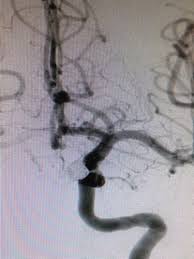

여기까지는 뇌출혈이 있는지를 확인하는 검사이고, 실제 파열된 뇌동맥류의 치료계획을 세우기 위해서는 뇌혈관 조영술을 시행하여 동맥류의 발생부위와 크기, 방향, 뇌혈관 상태 등 향후 치료와 수술에 대한 계획을 세운다고 한다.

대부분은 3차원 CT 및 MRI 검사로 발견할 수 있는데, 뇌동맥류가 발견되면 뇌혈관조영술을 시행하여 동맥류의 발생부위와 크기, 방향, 뇌혈관의 상태 등 향후 치료와 수술에 대한 계획을 세운다고 한다.